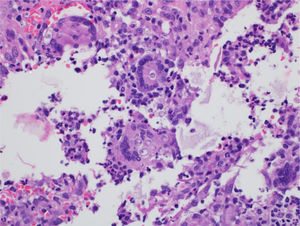

The diagnostic hypotheses were histoplasmosis, cryptococcosis, and paracoccidioidomycosis. The histopathological analysis of a skin lesion biopsy showed epidermal hyperplasia and granulomatous and dermal suppurative inflammatory infiltrate, with the presence of fungal elements inside giant cells (Fig. 2). Grocott-Gomori staining showed multi-budding fungal cells, characteristic of the Paracoccidioides spp genus (Fig. 3).